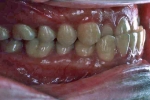

初診時

|